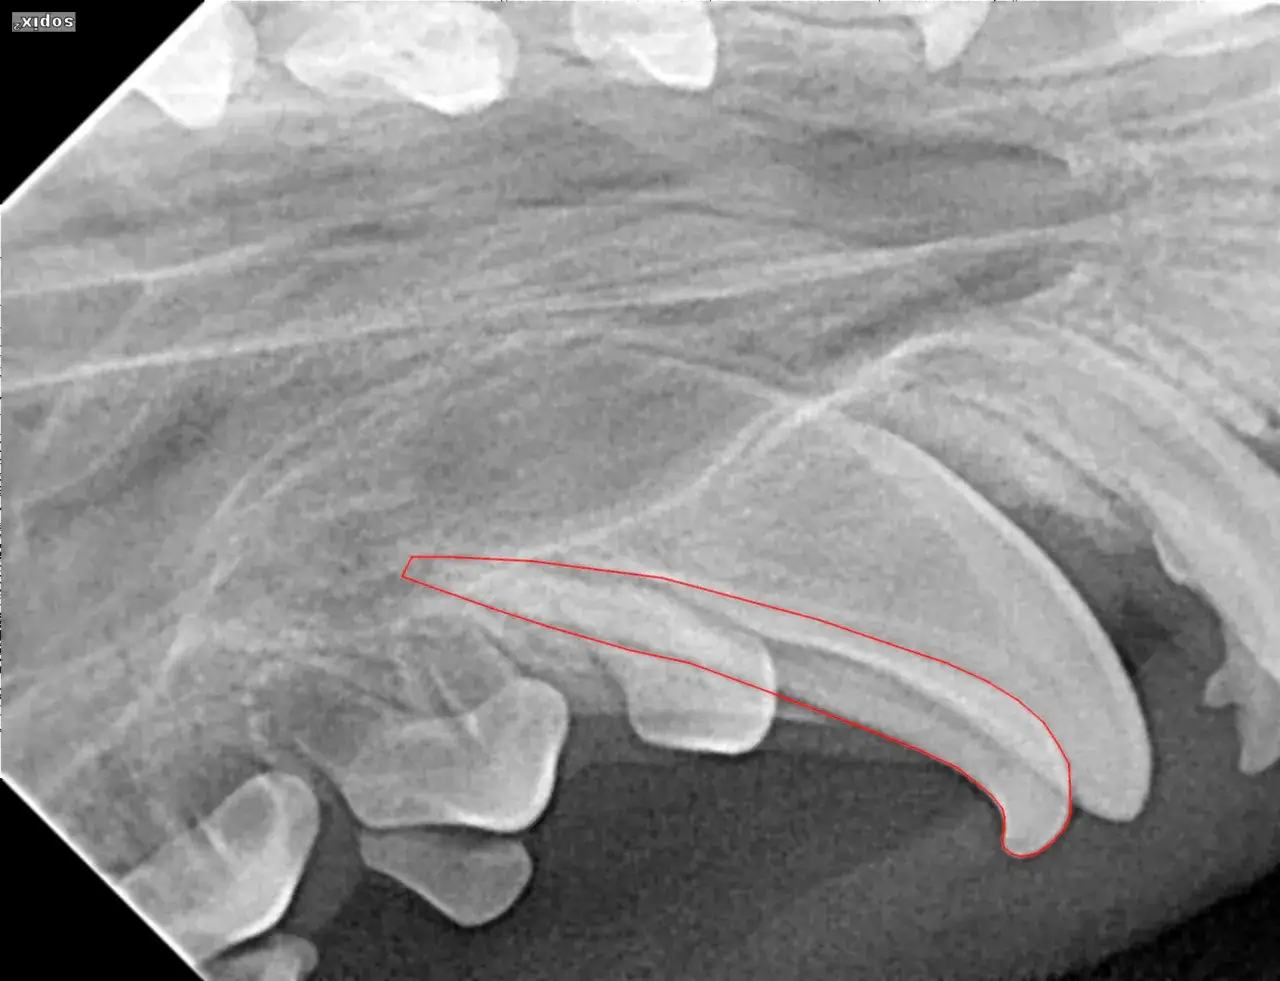

USG jamy brzusznej: Dlaczego zobrazowanie nadnerczy i wątroby jest tak istotne?

Oprócz badań krwi i moczu, badanie ultrasonograficzne (USG) jamy brzusznej jest niezwykle cennym narzędziem diagnostycznym. Pozwala mi ono na bezpośrednią ocenę wyglądu i wielkości nadnerczy. W przypadku formy nadnerczowej często widzimy powiększone jedno nadnercze, często z widocznym guzem. W formie przysadkowej nadnercza mogą być obustronnie powiększone lub mieć prawidłowy rozmiar. USG pozwala także ocenić wątrobę pod kątem jej powiększenia (hepatomegalii), co, jak już wiemy, jest częstym objawem zespołu Cushinga. To badanie dostarcza nam ważnych informacji anatomicznych, które uzupełniają wyniki testów hormonalnych.